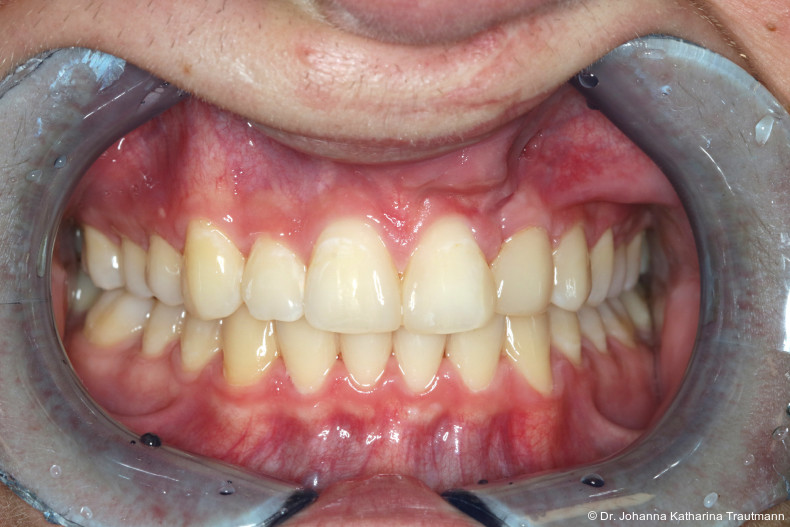

Das Fernröntgenseitenbild zeigte eine skelettale Klasse IIAnomalie mit einem Wits von 5,6 mm, bei einer tiefen Konfiguration (ML NL = 16,5°) mit bialveolär retrudierten Fronten (OK1NA = 5,9°; UK1NB = 10,4°), was sich auch in der Modellanalyse widerspiegelte. Hier zeigte sich zudem ein schmaler Oberkiefer mit multiplen Kippungen und Rotationen in der Front, einem hypoplastischem 22 sowie einer Mesialwanderung des 16. Des Weiteren zeigte sich eine asymmetrische Bisslage mit 1 PB distal rechts und ½ PB distal links bei einem Overjet von 2,5 mm sowie einem Overbite von 5 mm. Während im Unterkiefer bereits die zweite Zahnwechsel phase begonnen hatte, zeigte sich im Oberkiefer noch kein Wechsel in den Stützzonen. Gerade bei Patienten mit Spaltbildungen ist eine engmaschige Überwachung des Durchbruchs der oberen Eckzähne essenziell. Während bei der Allgemeinbevölkerung die Prävalenz von verlagerten Eckzähnen bei ca. 2,8 Prozent liegt2, ist diese bei Patienten mit Lippen-Kiefer-Gaumen-Spalten um den Faktor 10 erhöht.3, 4 Als klassische Risikofaktoren gelten zudem Platzmangel, transversale Enge aber auch Fehlstellungen, Nichtanlagen oder Hypoplasien der zweiten Schneidezähne. Diese übernehmen normalerweise die Funktion der Leitschiene für den S-förmigen Durchbruch der Eckzähne. Im vorliegenden Patientenfall kommen also mehrere Risikofaktoren für eine Verlagerung zusammen, was die rechtzeitige Diagnostik zur Abklärung einer Durchbruchsproblematik rechtfertigt. Da im Spaltbereich auch zusätzlich ein ausgeprägtes Knochendefizit vorliegen könnte, sollte auch immer die Option einer sekundären Osteoplastik abgewogen werden, deren Indikation und Timing optimal zum Durchbruch der Canini angepasst werden sollte.5

Längere Retentionszeiten ohne odontoplastischen Umbau können das Risiko eines Rezidivs des Zahnes 22 erhöhen. Dennoch ist häufig eine Abheilphase nach der Multibrackettherapie erforderlich, da sich gingivale Entzündungen oft erst nach ein bis drei Monaten vollständig zurückbilden.19–21 Um diesen Zeitraum zu überbrücken wurde an 22 die Kunststoffbasis der DVP (Doppel vorschubplatte) zur Retention sowohl mesial als auch distal extendiert. Schließlich wurden die Zähne 11, 21 und 22 kompositrestaurativ angeglichen, wodurch ein sehr gutes ästhetisches Ergebnis erzielt wer den konnte. Aufbauten mit Komposit bieten eine gute Möglichkeit, bei maximaler Schonung der Zahnhartsubstanz hypoplastische Zähne langfristig zu versorgen, und zeigten in ZehnJahresFollowups hohe Überlebensraten. Entscheidend ist hierbei eine ausgeglichene okklusale Lastverteilung, die mit hilfe einer physiologischen Frontzahnabstützung und gesicherten Okklusion durch die kieferorthopädische Vorbehandlung erreicht werden kann.22

Zur objektiven Quantifizierung des Behand lungsergebnisses wurde der Peer Assess ment Rating(PAR)Index erhoben.23 Im vorliegenden Fall konnte der PAR-Wert von 25 auf zwei reduziert werden, was einer Verbes serung von 92 Prozent entspricht und als hoch wertiges okklusales Ergebnis einzustufen ist.24 Zur Vorhersage der Langzeitstabilität bei Spalterkrankungen lässt sich dieser Fall in die Gruppe 1 des GOSLON Yardstick Index ein ordnen. Dieser sagt eine exzellente Langzeitstabilität vorher.25 Auch der Patient zeigte sich mit dem Ergebnis sehr zufrieden. Während der anderthalbjährigen Retentionsphase erfolgte zusätzlich eine ästhetische Nasenkorrektur zur Aufrichtung des linken Nasenflügels, wodurch neben der dentalen auch die extraorale Rehabilitation erfolgreich abgeschlossen werden konnte.